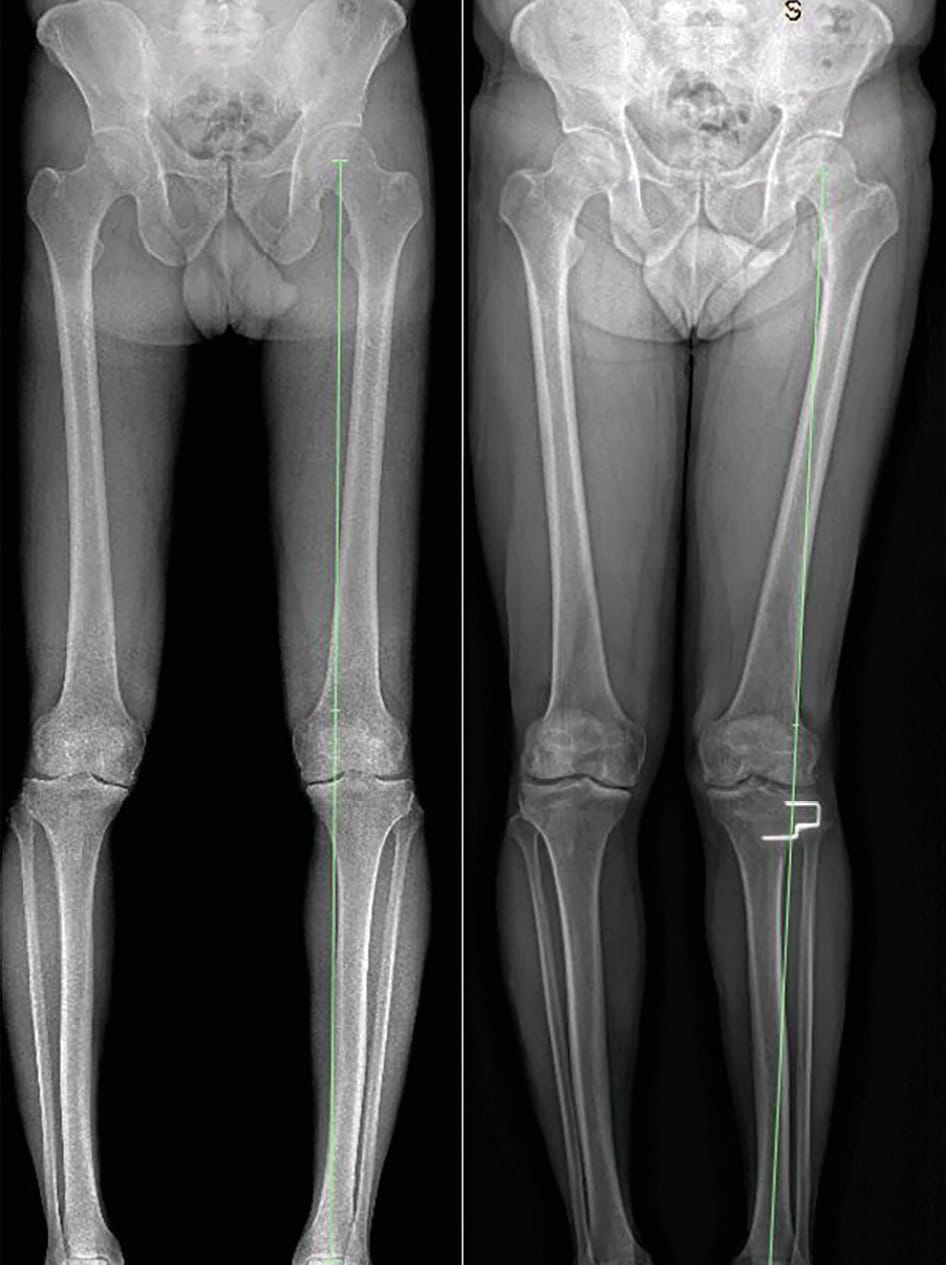

High tibial osteotomy (HTO) is a well-established surgical technique for the management of medial compartment osteoarthritis of the knee in the young, active patient; in this group, partial and total knee replacements are reported to have high failure rates [1] Australian Orthopaedic Association National Joint Replacement Registry. Annual Report 2017. Available at: https://aoanjrr.sahmri.com/documents/10180/397736/Hip%2C%20Knee%20%26%20Shoulder%20Arthroplasty. Accessed March 10, 2018. 2017.. The purpose of HTO is to shift the lower limb mechanical axis laterally to redistribute weight-bearing forces away from the worn medial compartment and through the preserved lateral compartment (Figure 1). This relieves pain and can encourage fibrocartilagenous regrowth over the eburnated medial femoral condyle. When successful, HTO permits high levels of activity, has excellent long term outcomes, and is readily revised to TKR if required. Furthermore, TKR performed after HTO has similar outcomes to primary TKR [2] Ramappa M, Anand S, Jennings A. Total knee replacement following high tibial osteotomy versus total knee replacement without high tibial osteotomy: a systematic review and meta analysis. Archives of orthopaedic and trauma surgery. 2013 Nov;133(11):1587-93. PubMed PMID: 23959070..

Pre-operative planning is undertaken with a long leg weight-bearing alignment film. The width of the plateau is calculated and the current mechanical axis assessed - this is typically medialised in the patient with varus osteoarthritis. Using a transverse axis across the surface of the tibial plateau, and ignoring osteophytes, we calculate the point 40% across the plateau from the lateral margin, and mark this as our intended weight bearing point. Two lines are drawn to this point – first from the femoral head centre, and the second from the middle of the talar dome. The angle thus subtended will be the osteotomy angle, or the angle of the resected bony wedge. The goal is to produce a post-operative weight bearing line that falls through the intended weight bearing point, at 40% laterally on the tibial plateau.